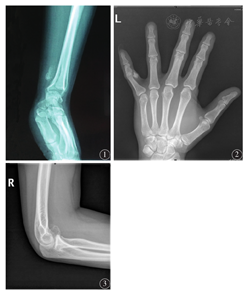

3例患者术后分别随访39、28、18个月均未复发和转移。X线检查显示:3例均为单发性肿块,表现为附着骨皮质表面的不规则、不均匀钙化或骨化病变,边界清晰,宿主骨骨皮质连续完整,病变与附着骨骨髓腔无延续(图1、图2、图3)。大体检查:送检物均为破碎组织,内含骨及软骨组织。光学显微镜下观察:3例病变镜下特征类似,均由分化成熟的软骨、骨以及纤维组织混合构成,三种成分的排列无规律;软骨细胞丰富,细胞具有轻度异型性,核增大,可见核仁与少量双核细胞;软骨化骨成分和软骨岛与骨小梁之间的纤维组织均分化成熟,缺乏细胞学异型性;3例病变组织中均见特征性"蓝骨"成分(图4)。

4A:病灶边界清楚×40;4B:病灶由分化成熟的骨、软骨和纤维组织混杂组成×100;4C:特征性的"蓝骨" ×200;4D:软骨细胞具有轻度异型性,见少量双核细胞×400